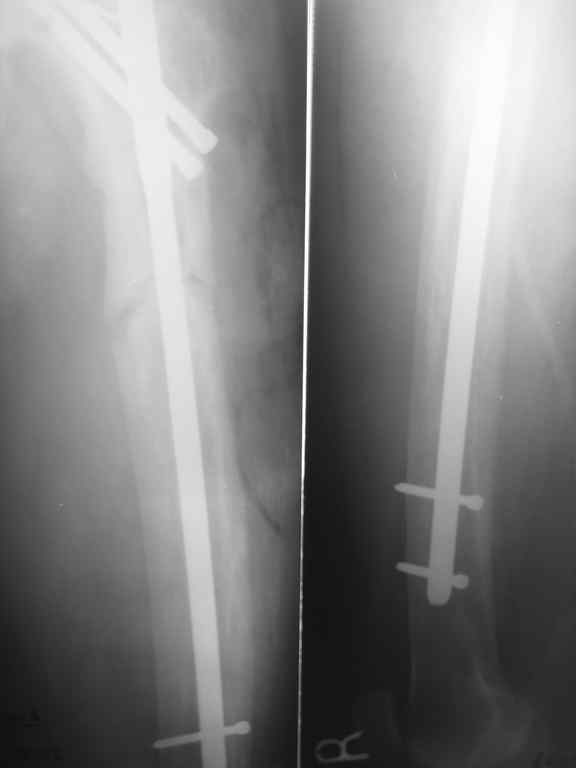

Пациент 82 лет, поступил через 5 мес. с несросшимся переломом после открытого интрамедуллярного остеосинтеза. Выполнили реостеосинтез стержнем 12 мм. ( мах. доступного нам в 2003 г.) Через 4 мес динамизация. В течении 2х лет сращения нет, тем не менее конечность опорна (ходит с тростью). От очередного реостеосинтеза отказались из-за сопутств. патологии.

Еще один пример. Пациентка с юга России, прислала рентгенограммы через год. На сегодня прошло 2 г. 8 мес. после операции. Несмотря на не очень убедительный процесс сращения, пациентка ходит. Учитывая остеопороз при Педжете, решили, что динамизировать вообще не нужно.

При переломах на фоне болезни Педжета металлоконструкция часто служит эндопротезом, несущим нагрузку. Динамизация индивидуальна,- по рентген-динамике. Основной упор- на медикаментозную терапию- см. канд. дисс. Колондаева А.Ф.

Стержень можно было бы поставить подлиннее.

Анатолий Леонидович Баранецкий совершенно прав. Сращения ждать надо очень долго (несколько лет). Главное - гвоздь попрочнее и потолще. Раньше использовали мощный 4-гранный штифт ЦИТО. Можно и гвоздь с блокированием (блокировать только с одной стороны) - но ни в коем случае не полый. И ходить с тростью. Сейчас в России зарегистрирован очень хороший препарат (с декабря 2006 г.) - Акласта, по 100 мл - обычно хватает 1 (реже двух) инфузии для полной ремиссии (в Белоруссии он появился даже раньше, чем на Украине и в Россиии). Немного хуже Аредия, ее надо в сумме 180-240 мг, полная эффективность 84%. Все в\в кап. бисфосфонаты вызывают выраженную гипокальциемию. Поэтому приходится назначать по нескольку лет альфакальцидол под контролем Са крови (каждые 3-6 мес). Сперва по 6-8 капсул (капель), т.е 1,5-2,0 мкг, затем через 2-4 месяца - по 0,5-0,75 мкг. Препараты Са по 1-2 гр. в день, очень долго.